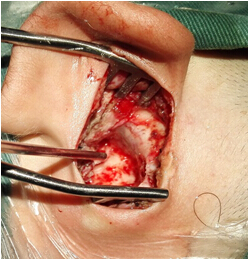

5.膽脂瘤清除后的乳突鼓室腔 6.術(shù)后傷口愈合

家屬帶患兒到市內(nèi)多家大醫(yī)院就診都告知手術(shù)風(fēng)險較大,病灶難以一次性清除干凈。患兒家屬抱著試試看的心態(tài)來我科就診,在我科主任及主治醫(yī)師詳細(xì)周密的診療計劃下,待炎癥控制后安排耳顯微外科手術(shù),一次性徹底清除留在患兒側(cè)顱底及中耳乳突腔內(nèi)的“定時炸彈”,并成功保護(hù)了患兒原有聽力,未出現(xiàn)面癱、耳后傷口感染及瘺口等術(shù)后并發(fā)癥,為我科耳顯微外科發(fā)展史上再添新亮。